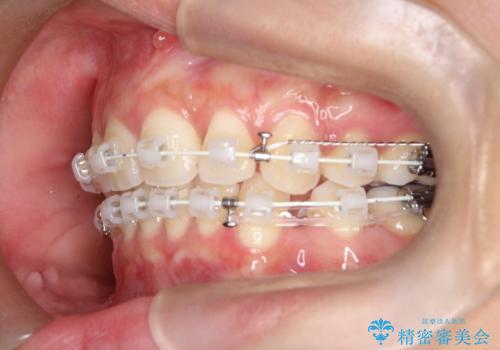

2. 【審美ワイヤー】口元を下げたいの治療中